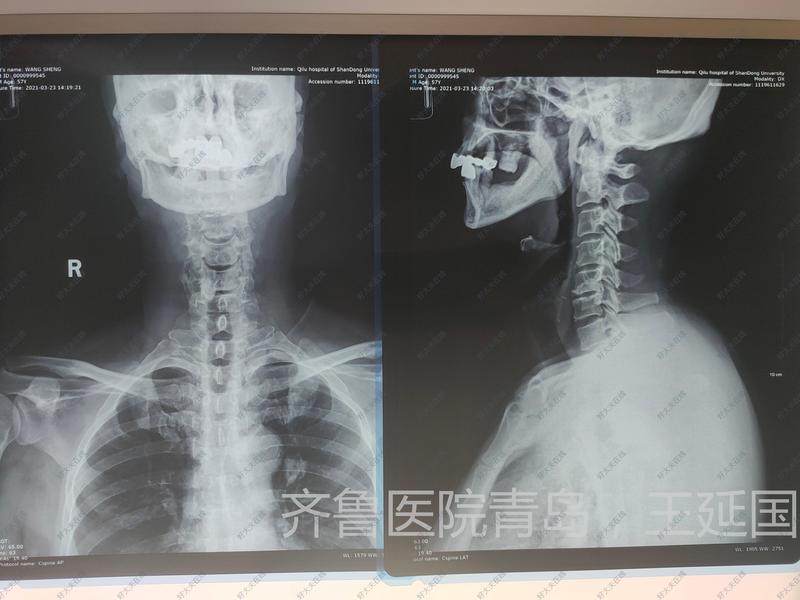

治療前患者四肢麻木無力,走路不穩(wěn)、容易走偏、足底彩棉感2年入院。入院查體可見患者雙下肢感覺減退,腱反射亢進(jìn),病理反射陽性。影像學(xué)檢查頸椎磁共振可見頸4/5、5/6椎間盤突出,壓迫硬膜囊,C4/5節(jié)段脊髓變性。診斷為脊髓型頸椎病。治療中手術(shù)行常規(guī)微創(chuàng)前路椎間盤切除植骨融合內(nèi)固定術(shù),手術(shù)于3D顯微鏡下進(jìn)行,手術(shù)操作更加清晰、安全,手術(shù)順利完成,出血10ml,患者手術(shù)結(jié)束麻醉清醒后四肢活動(dòng)正常,自覺感覺良好。治療后治療后0天患者術(shù)后第一天佩戴下床活動(dòng),自覺術(shù)后雙下肢較前有力,走路踏實(shí)。腰背部疼痛也消失。患者非常滿意。術(shù)后3天出院。3D顯微鏡能讓手術(shù)醫(yī)生如虎添翼,使手術(shù)更加安全、有效,術(shù)后恢復(fù)更快。